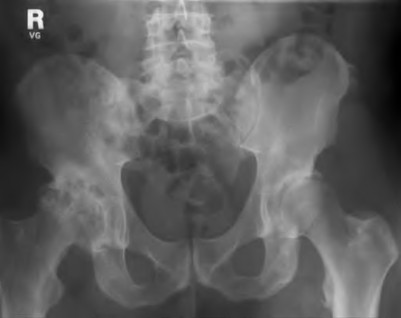

A 45-year-old female with developmental dysplasia of the hip (DDH) presents for THA. Preoperative radiographs show the femoral head is subluxated, with 80% proximal migration relative to the height of the normal true acetabulum. Based on the Crowe classification, what type of dysplasia does she have?

Explanation